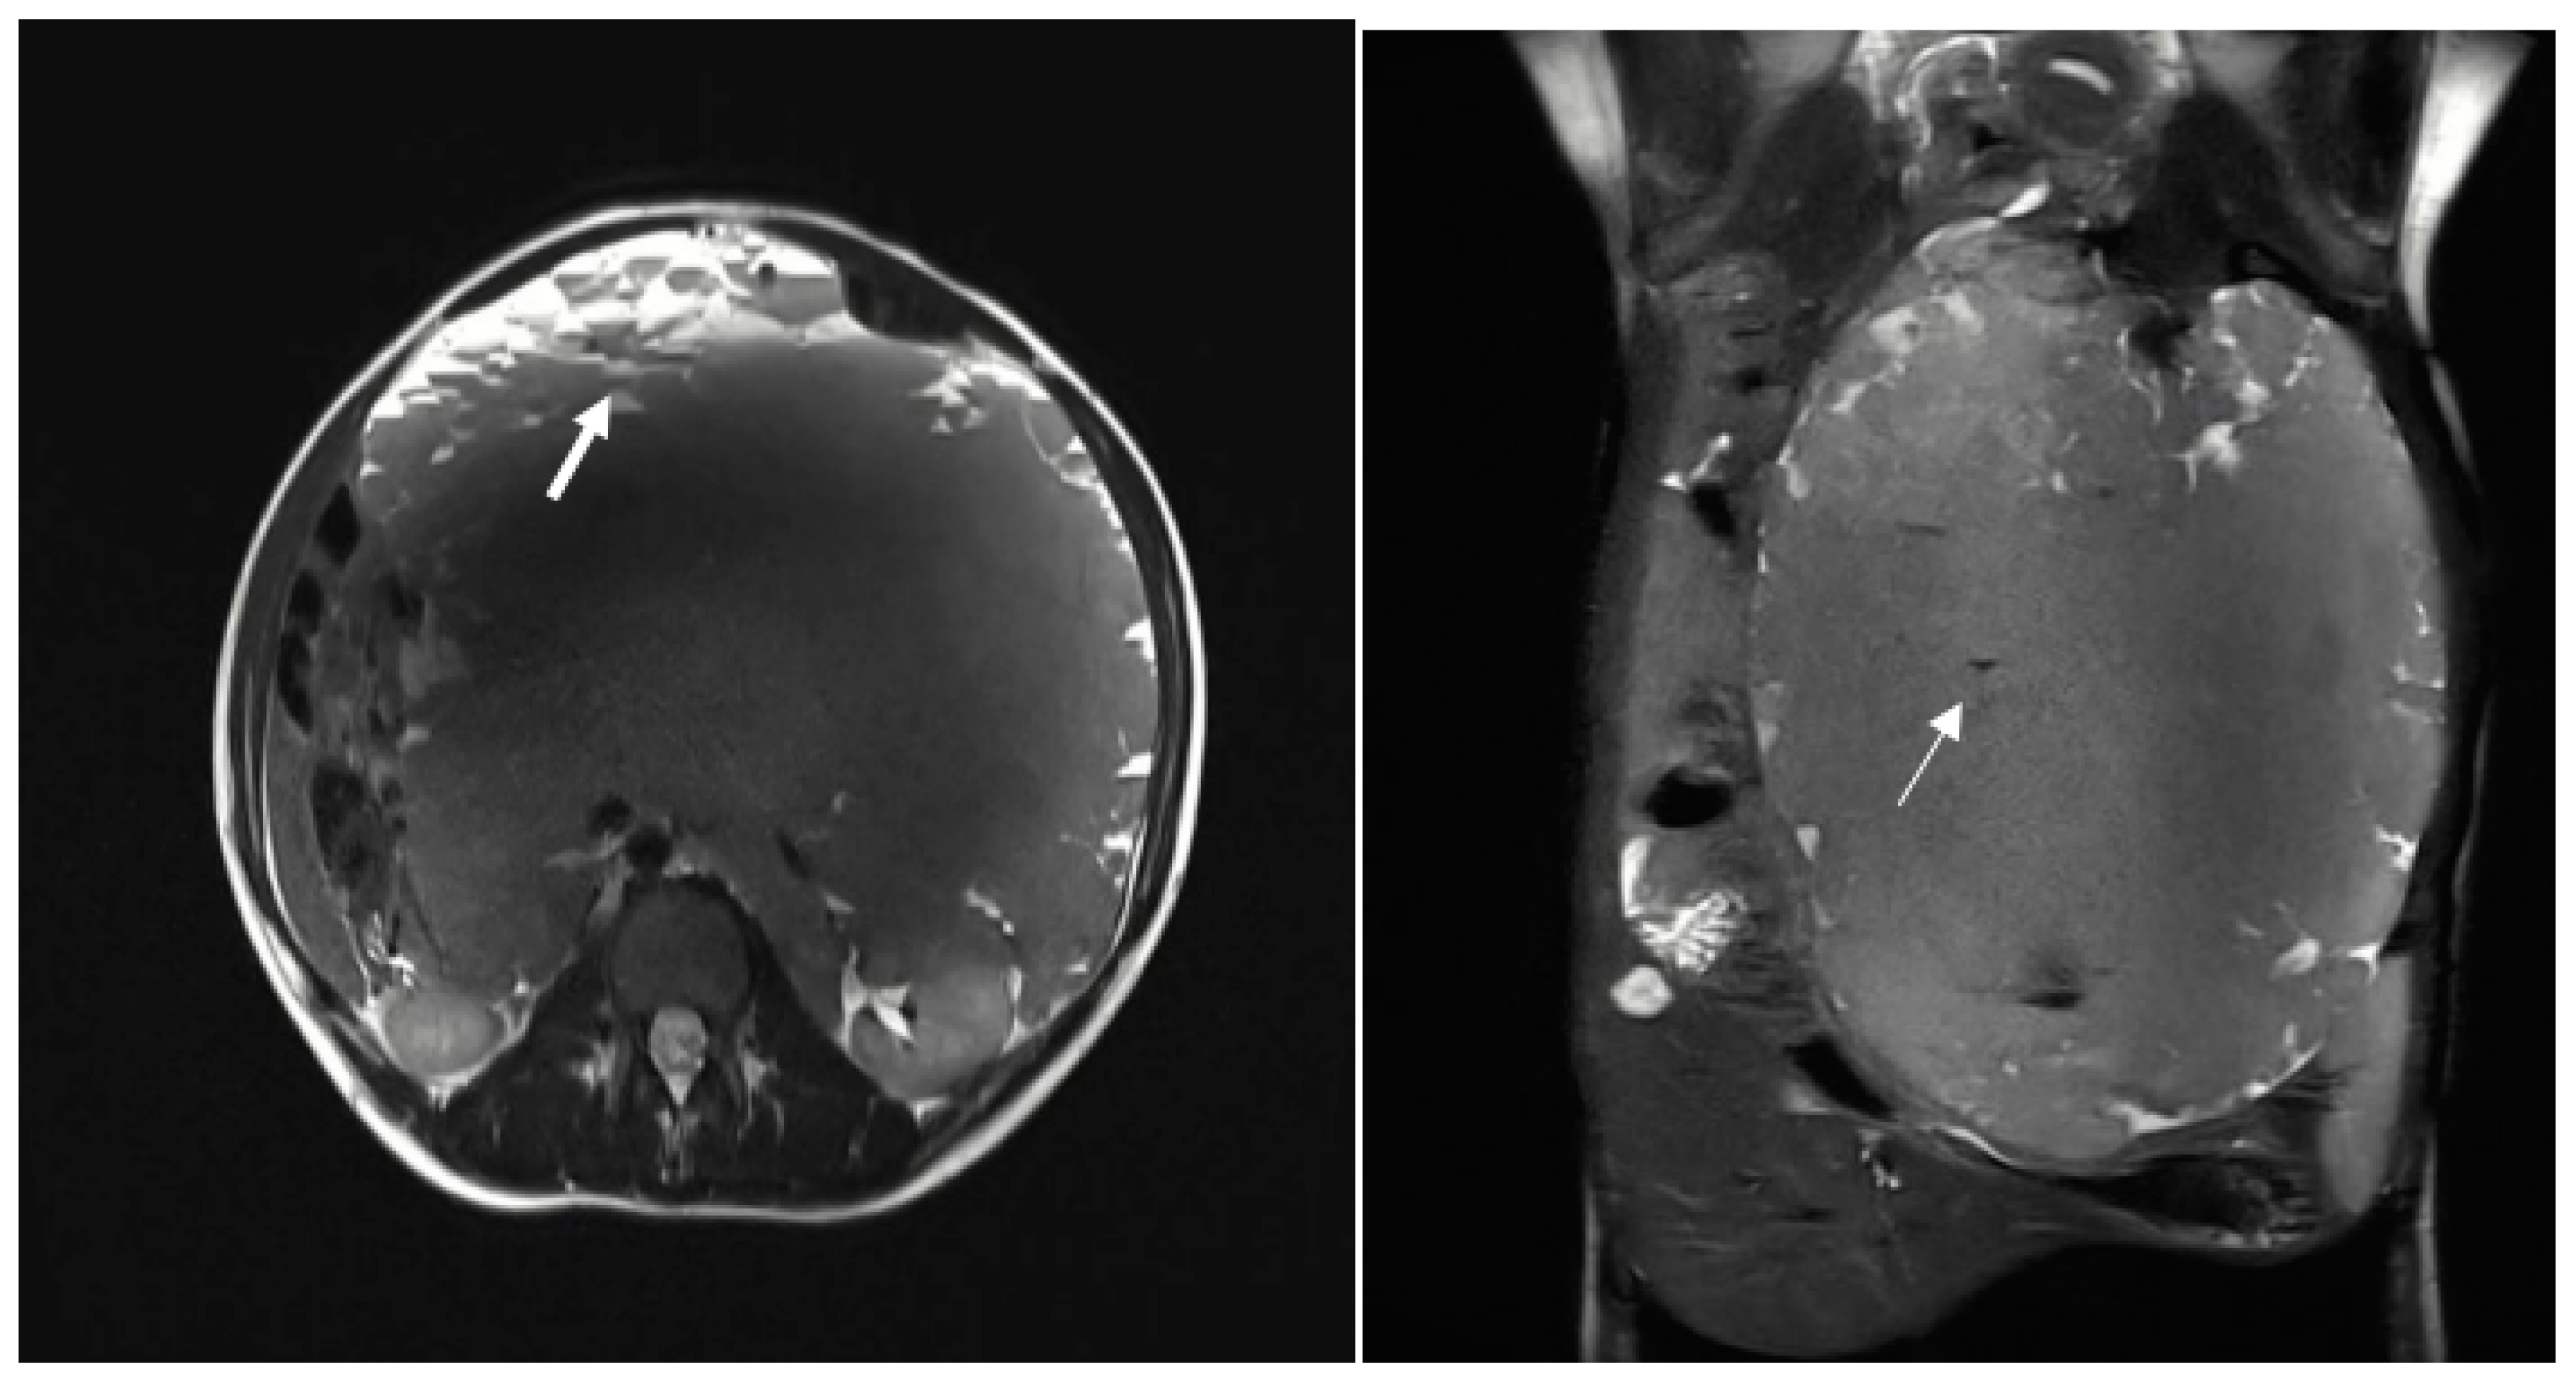

Figure 2. The multiloculated mass shows variable signal intensity on T2 sequences and presents cystic formations peripherally, exhibiting fluid-debris levels (thick arrow). Some calcified spots low T2WI signals were also noted within the mass (thin arrow).

The patient was subsequently admitted for further evaluation, and an abdominal MRI was performed. Imaging sequences included T2 weighted sequences and T1 weighted sequences, with and without fat suppression. However, due to limited patient compliance, the study was interrupted before the contrast agent administration. Despite these limitations, MRI confirmed the presence of a large multiloculated mass with peripheral cystic components exhibiting fluid-debris levels (Figure 2).

On MRI, these malformations are usually well-defined, lobulated, and septated. They predominantly show low signal intensity on T1-weighted images and high signal intensity on T2-weighted images. The signal intensity can vary depending on the amount of protein or hemorrhage in the lesion. Occasionally, the content may appear brighter than muscle on T1-weighted images, particularly in cases where the cyst contains protein or blood. Generally, the enhancement after contrast medium agent administration is visible only in the septa and solid components. However, if there is inflammation, also septa surrounding areas may show significant enhancement. [10]